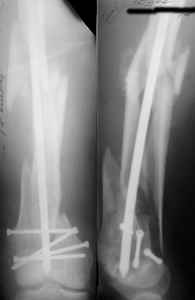

A new toy is more interesting and fashionable. And anyway it is not panacea, i have already seen presentations with LISS failures like the attached one presented by D.Seligson. And people also demonstrated incisions say that the method is not so LESS invasive as it supposed to be.

KEMMD> (I do not have any financial interest with any of the

Maybe we here do - if equal or better results are reached with $100 implant, why use the $1100 one?